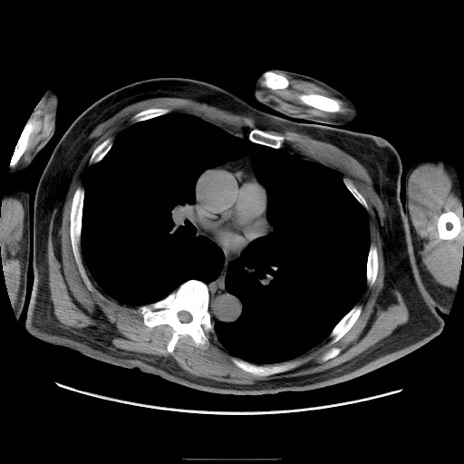

症例22(横断像)

【症例】50歳代男性

【主訴】腹痛

【現病歴】AVMからの被殻出血のため回復期リハ病棟入院中。 本日午後3時頃急に下腹部痛が出現した。

【既往歴】AVM、被殻出血、虫垂炎、高血圧

【身体所見】意識晴明、左半身不全麻痺、会話の理解は良好、36.5°C、腹部:膨隆、全体に板状硬、下腹部正中に圧痛点あり、反跳痛-、筋性防御不明、右下腹部にope scar

【データ】WBC 9400、CRP 0.06